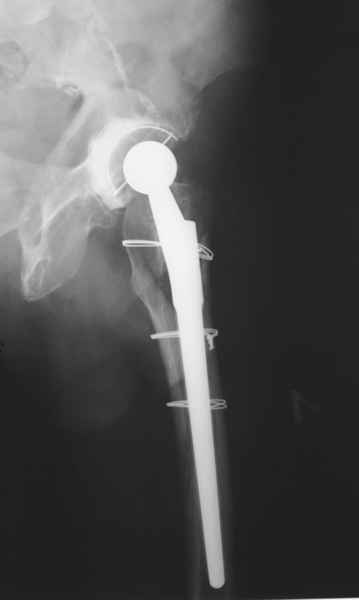

2. Применение ножки дистальной фиксации, мы отдаем предпочтение ножке Вагнера с фиксацией проксимального отдела на ножке. Более травматичное вмешательство, но при стабильной фиксации ножки реабилитация идет в обычном режиме.

Хочется показать два подобных случая, П-ка З. 72 лет и п-т Г. 80 лет. Сразу принимаю замечание, что это были ножки цементной фиксации, просто под руками не было бесцементника.